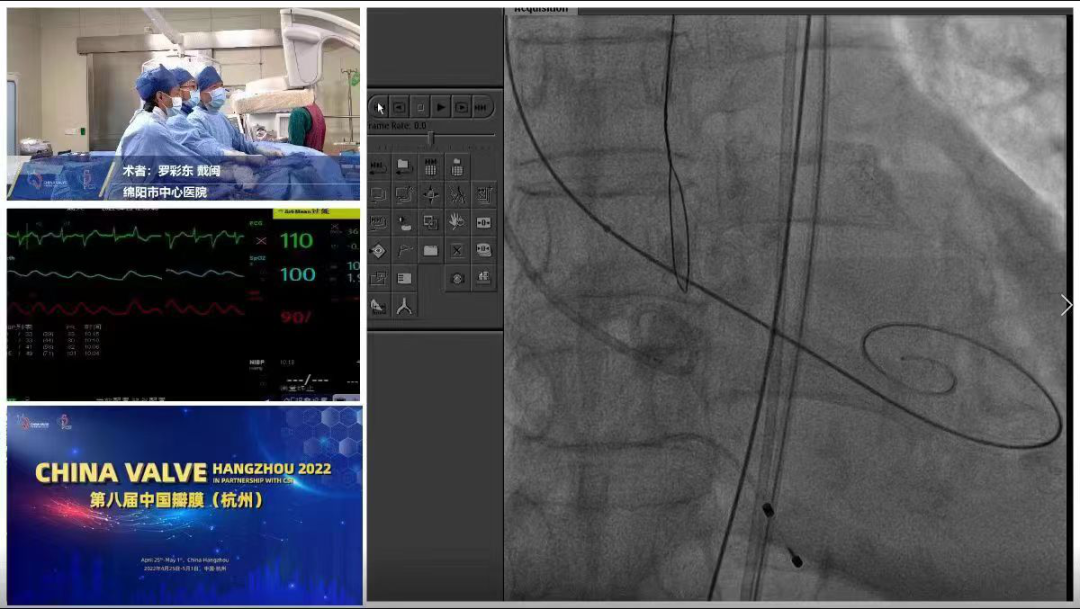

手术过程概览